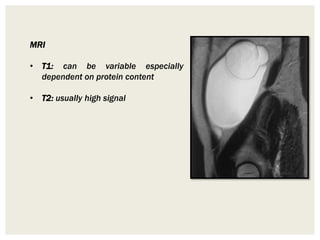

MRI

• T1: can be variable especially

dependent on protein content

• T2: usually high signal